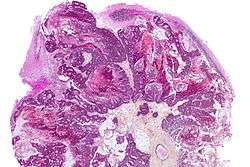

Brain metastasis

A brain metastasis is a cancer that has metastasized (spread) to the brain from another location in the body.[1] As primary cancer treatments such as surgery, radiation therapy and chemotherapy have become more effective in the past few decades, people with cancer are living longer after initial treatment than ever before. However, brain metastases still occur in many patients months or even years after their original cancer treatment. Brain metastases have a poor prognosis for cure, but modern treatments are allowing patients to live months and sometimes years after the diagnosis.[2]